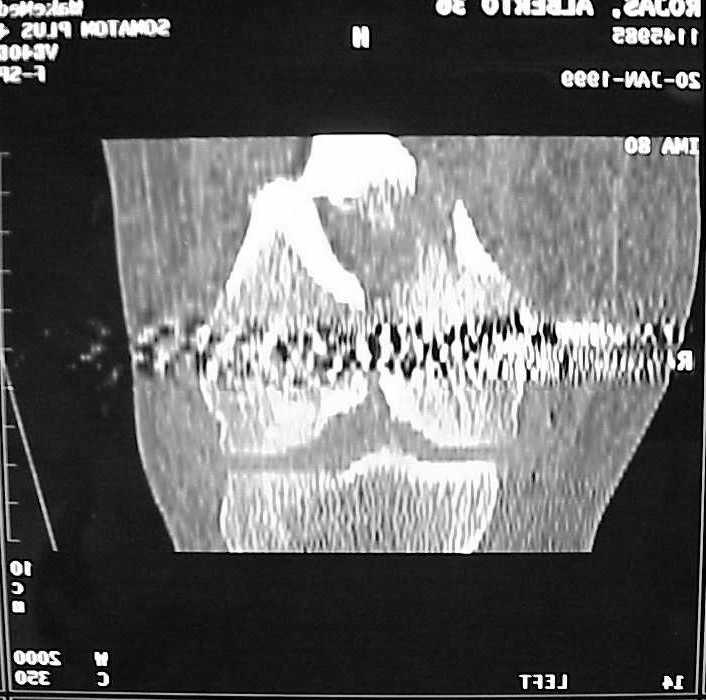

See attached case that was done several years ago before LISS. He had comminuted trochlea and anterior blocking screws were used to prevent anterior IMN cut-out.

Насчет стабильности для ранней нагрузки, конечно, сомнительно, но при таком повреждении ранняя нагрузка противопоказана в любом случае. Для ранних движений Должно хватить. Снимки в следующем сообщении.

воспользовались для репозиции, см. приложение.